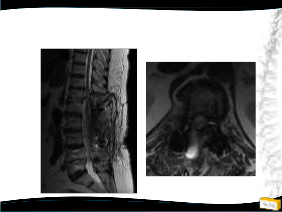

Olgu

• 64y, K

• Bel ve her iki bacak ağrısı

• NM normal

Yapılan Ameliyat: L1-L5 dekompesyon + transpediküler stabilizasyon

• Bel ağrısı, bacaklarında güçsüzlük,

3/5 paraparezi, üriner retansiyon

1. Op: Torakotomiyle T12-L1 diskektomi